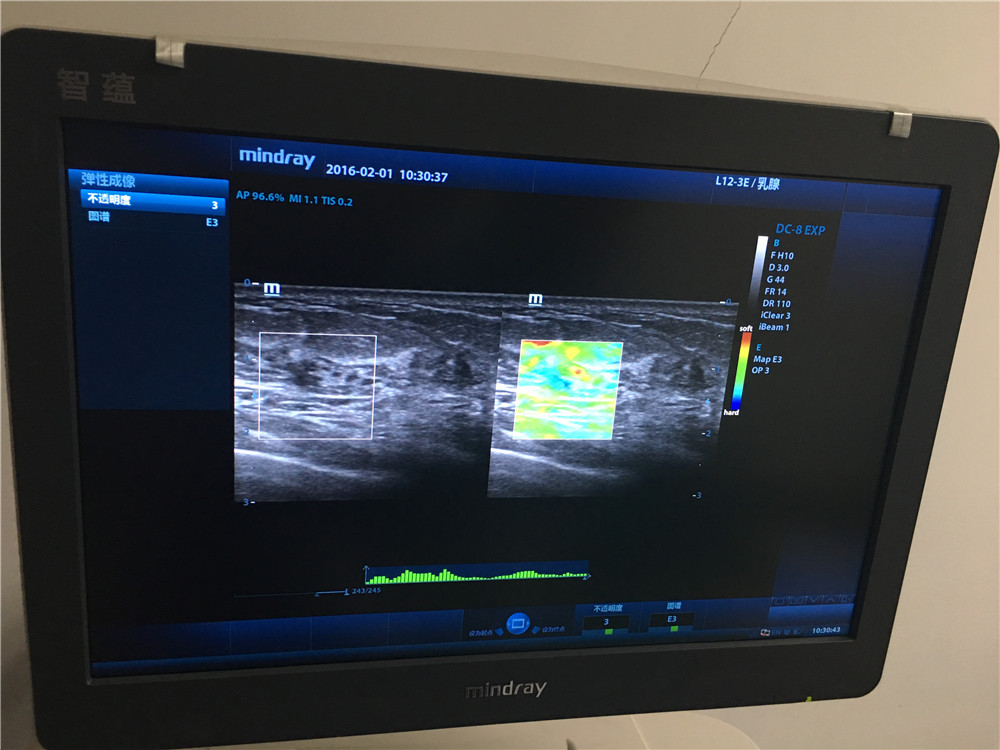

为进一步提高乳腺检查的敏感性和诊断的准确性,我院功能科在全市率先引进弹性成像这一辅助新技术,为早期诊断、鉴别乳腺肿瘤的良、恶性及早期治疗提供的一种新的有效途径。 作为一种全新的成像技术,弹性成像扩展了超声诊断理论的内涵和超声诊断范围,弥补了常规超声的不足,能更生动的显示、定位病变及鉴别病变性质,使现代超声技术更为完善。实时组织弹性成像不仅能帮助早期发现不易触及的微小及深在的病灶,在识别传统灰阶声像图上难以发现的病变浸润区域上也有优势,还能鉴别一些临床上较难诊断的乳腺病灶,如不典型的乳腺病及炎性病变。并且,如果弹性成像图与灰阶声像图上肿瘤的大小比较确可作为一种可靠的检测指标,那么临床早期发现恶性乳腺癌的比率将大大提高,需要接受活检以确定良恶性的患者数也将大大减少,既可帮助减轻社会医疗保健的经济负担,也可减轻患者自身身体和心理上的痛苦。其在临床上的应用包括:1.癌症的早期诊断;2.病变的良性、恶性判断;3.癌变扩散区域的确定;4.治疗效果的确认。

组织弹性成像除了在乳腺疾病方面研究较为深入,技术成熟外,目前还应用于前列腺、甲状腺等小器官,可有效鉴别实质性肿瘤的良恶性,对于恶性病变诊断具有较高的特异性和敏感性。另外还应用于肝纤维化的诊断、局部心肌功能评价以及高强度聚焦超声与射频消融引起的损害的检测与评估。

超声弹性成像技术尽管起步伊始,但该技术提供了与传统影像学不同的,有助于临床诊断的新信息。随着弹性成像设备的不断完善及临床应用技能的不断成熟,超声弹性成像将在临床工作中发挥更加重要的辅助作用。